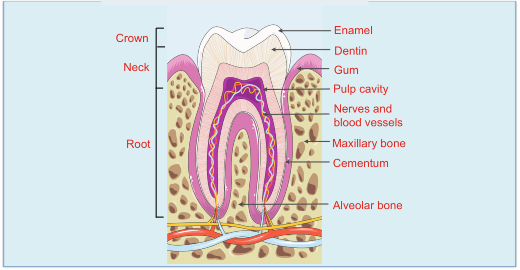

A tooth basically consists of two parts; the crown (outer portion visible in the mouth) and the root (the portion of the tooth below the gums). The outermost layer of the crown is enamel followed by dentine encasing the soft part that is the pulp in the centre.

The root has cementum as its outermost layer followed by dentine and pulp. The pulp consists of connective tissue, nerves and tiny blood vessels.

Whenever the central portion, that is the pulp is exposed to the external environment it gets infected and eventually dies. This could be because of caries (dental infection) or abrasion (because of overzealous brushing) or attrition (because of grinding of teeth) or because of fracture of teeth. If this dead tissue is not removed, the infection can spread to the apical bone and may cause a granuloma, cyst, abscess or even cellulitis or osteomyelitis.

The patient at this stage has to take a decision to either save the tooth or extract it.Saving means getting root canal treatment done which involves physical removal of the infected pulp or the dead tissue as the case might be. The next step is towiden and shape the canals,disinfect it and fill it with an inert material like gutta-percha. Subsequently the access cavity is filled with a suitable filling material. Now this tooth functions as any normal tooth except that there is no moisture supply to this tooth. This makes the tooth dry and brittle. Hence to reinforce it, a cap may be given which restores the tooth to normal anatomy and function.